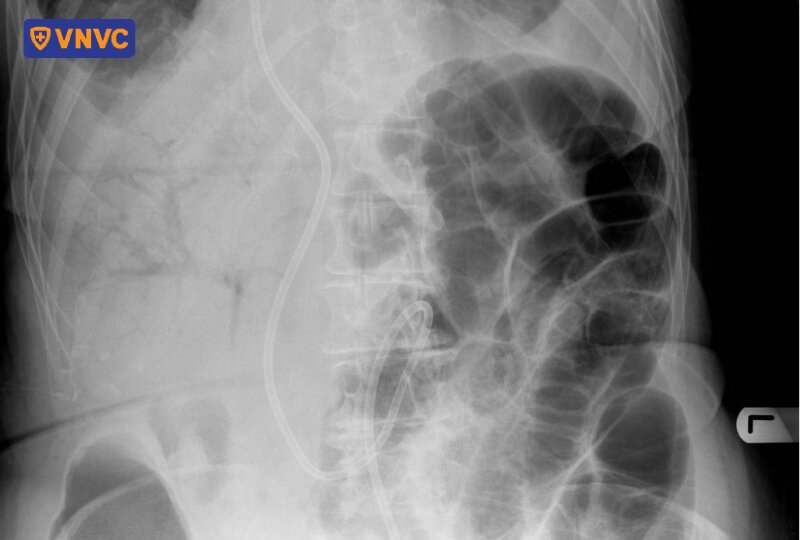

3. Chụp X-quang

Trên phim X-quang, khí tĩnh mạch cửa biểu hiện thông qua các phân nhánh trong suốt chiếu vào gan, theo hướng các mạch máu về phía gan. Phương pháp này cung cấp cái nhìn tổng quan, giúp phát hiện nhanh sự hiện diện của khí, mặc dù độ nhạy thấp hơn CT và siêu âm Doppler.